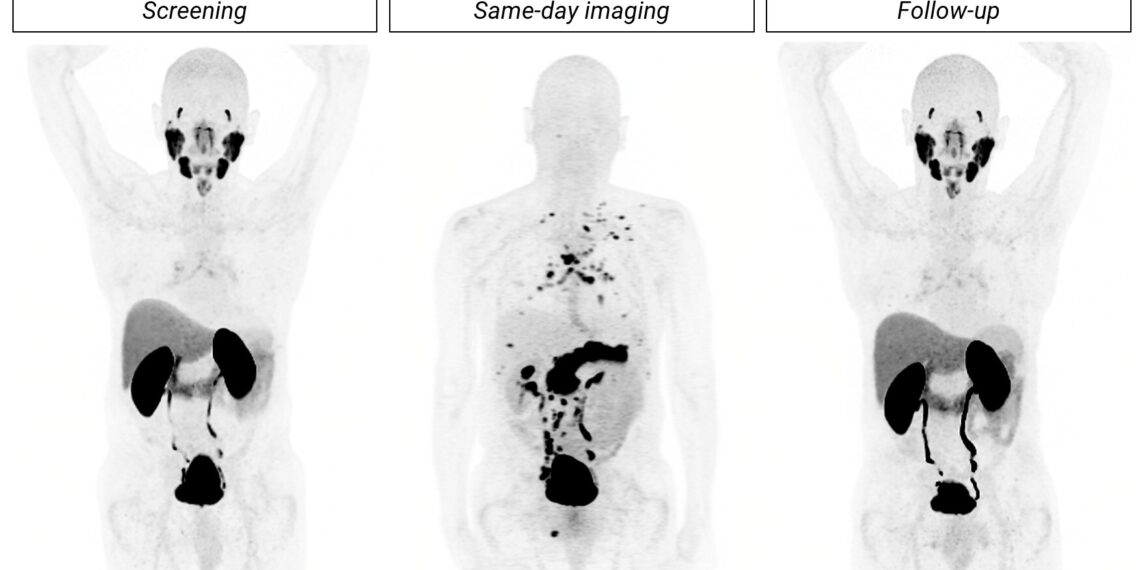

A participant with BCR of prostate cancer presented with a baseline PSA of 22.3 ng/mL, negative SOC PSMA PET (18F-DCFPyL, Figure 1, left image) and equivocal CT at screening. Imaging with 64Cu-SAR-Bombesin (middle image) revealed substantial disease burden with lesions detected in the pelvic LNs, extra-pelvic LNs, visceral/soft tissue, and bone. Subsequent biopsies of a right pelvic bone lesion and a supradiaphragmatic LN confirmed malignancy at both sites. A follow-up 18F-DCFPyL PET scan, conducted approximately 4 months after the screening with 18F-DCFPyL, failed to detect lesions in all regions except for the bone.

Figure 1. Detection of extensive metastatic disease by 64Cu-SAR-Bombesin in a participant with BCR of prostate cancer. The initial 18F-DCFPyL PSMA PET at screening was negative (left image), whereas same-day imaging with 64Cu-SAR-Bombesin (middle image) detected widespread disease, including lesions in the right pelvic bone and a supradiaphragmatic LN, which were confirmed as prostate cancer by biopsy. A follow-up 18F-DCFPyL scan approximately 11 weeks later (right image) was still unable to detect the extensive recurrence identified by the 64Cu-SAR-Bombesin scan. Maximum intensity projection of PET imaging. Images are shown with consistent scaling for visual comparison.